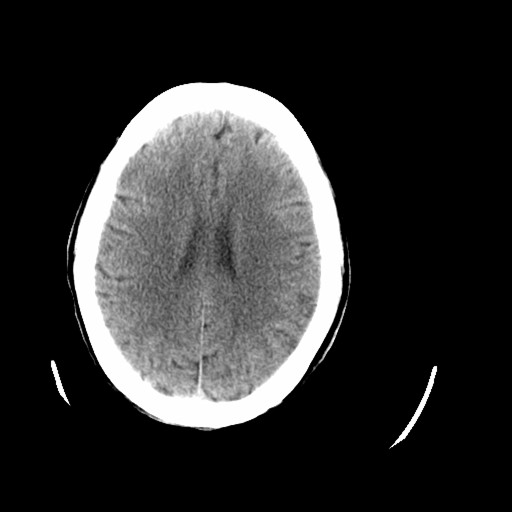

标题: CT16233:女,44岁,智障多年,现感头痛 [打印本页]

标题: CT16233:女,44岁,智障多年,现感头痛

小脑有啥病变?

老年脑,萎缩表现

脑萎缩

44岁  小脑表现为萎缩? 原因是什么呢?ct诊断上可报小脑萎缩吗?

橄榄桥小脑萎缩.左侧小脑脚腔梗.

为什么不考虑发育畸形呢

1)小脑萎缩。2)小脑蚓部发育不良。

橄榄桥小脑萎缩可能,建议mri进一步检查以进一步排查。

小脑萎缩征,原因待定.

橄榄桥小脑萎缩